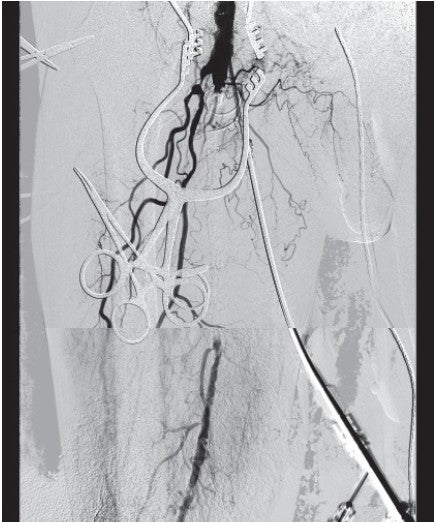

Iliac治療時に使用していた径8.0/長40 mmのノンコンプライアントバルーンで病変全体を拡張。良好な内腔確保ができたことを確認後、遠位部SFAから近位部SFAまで径7.0/長250 mm および径8.0/長50 mmのバイアバーン® ステントグラフトで病変をfull coverするかたちで留置。径7.0/長100 mmのハイプレッシャーバルーンで後拡張を行った。バイアバーン® ステントグラフト留置部の良好な拡張(図4)と、患趾までの良好な血流を確認し手技終了とした(図5)。